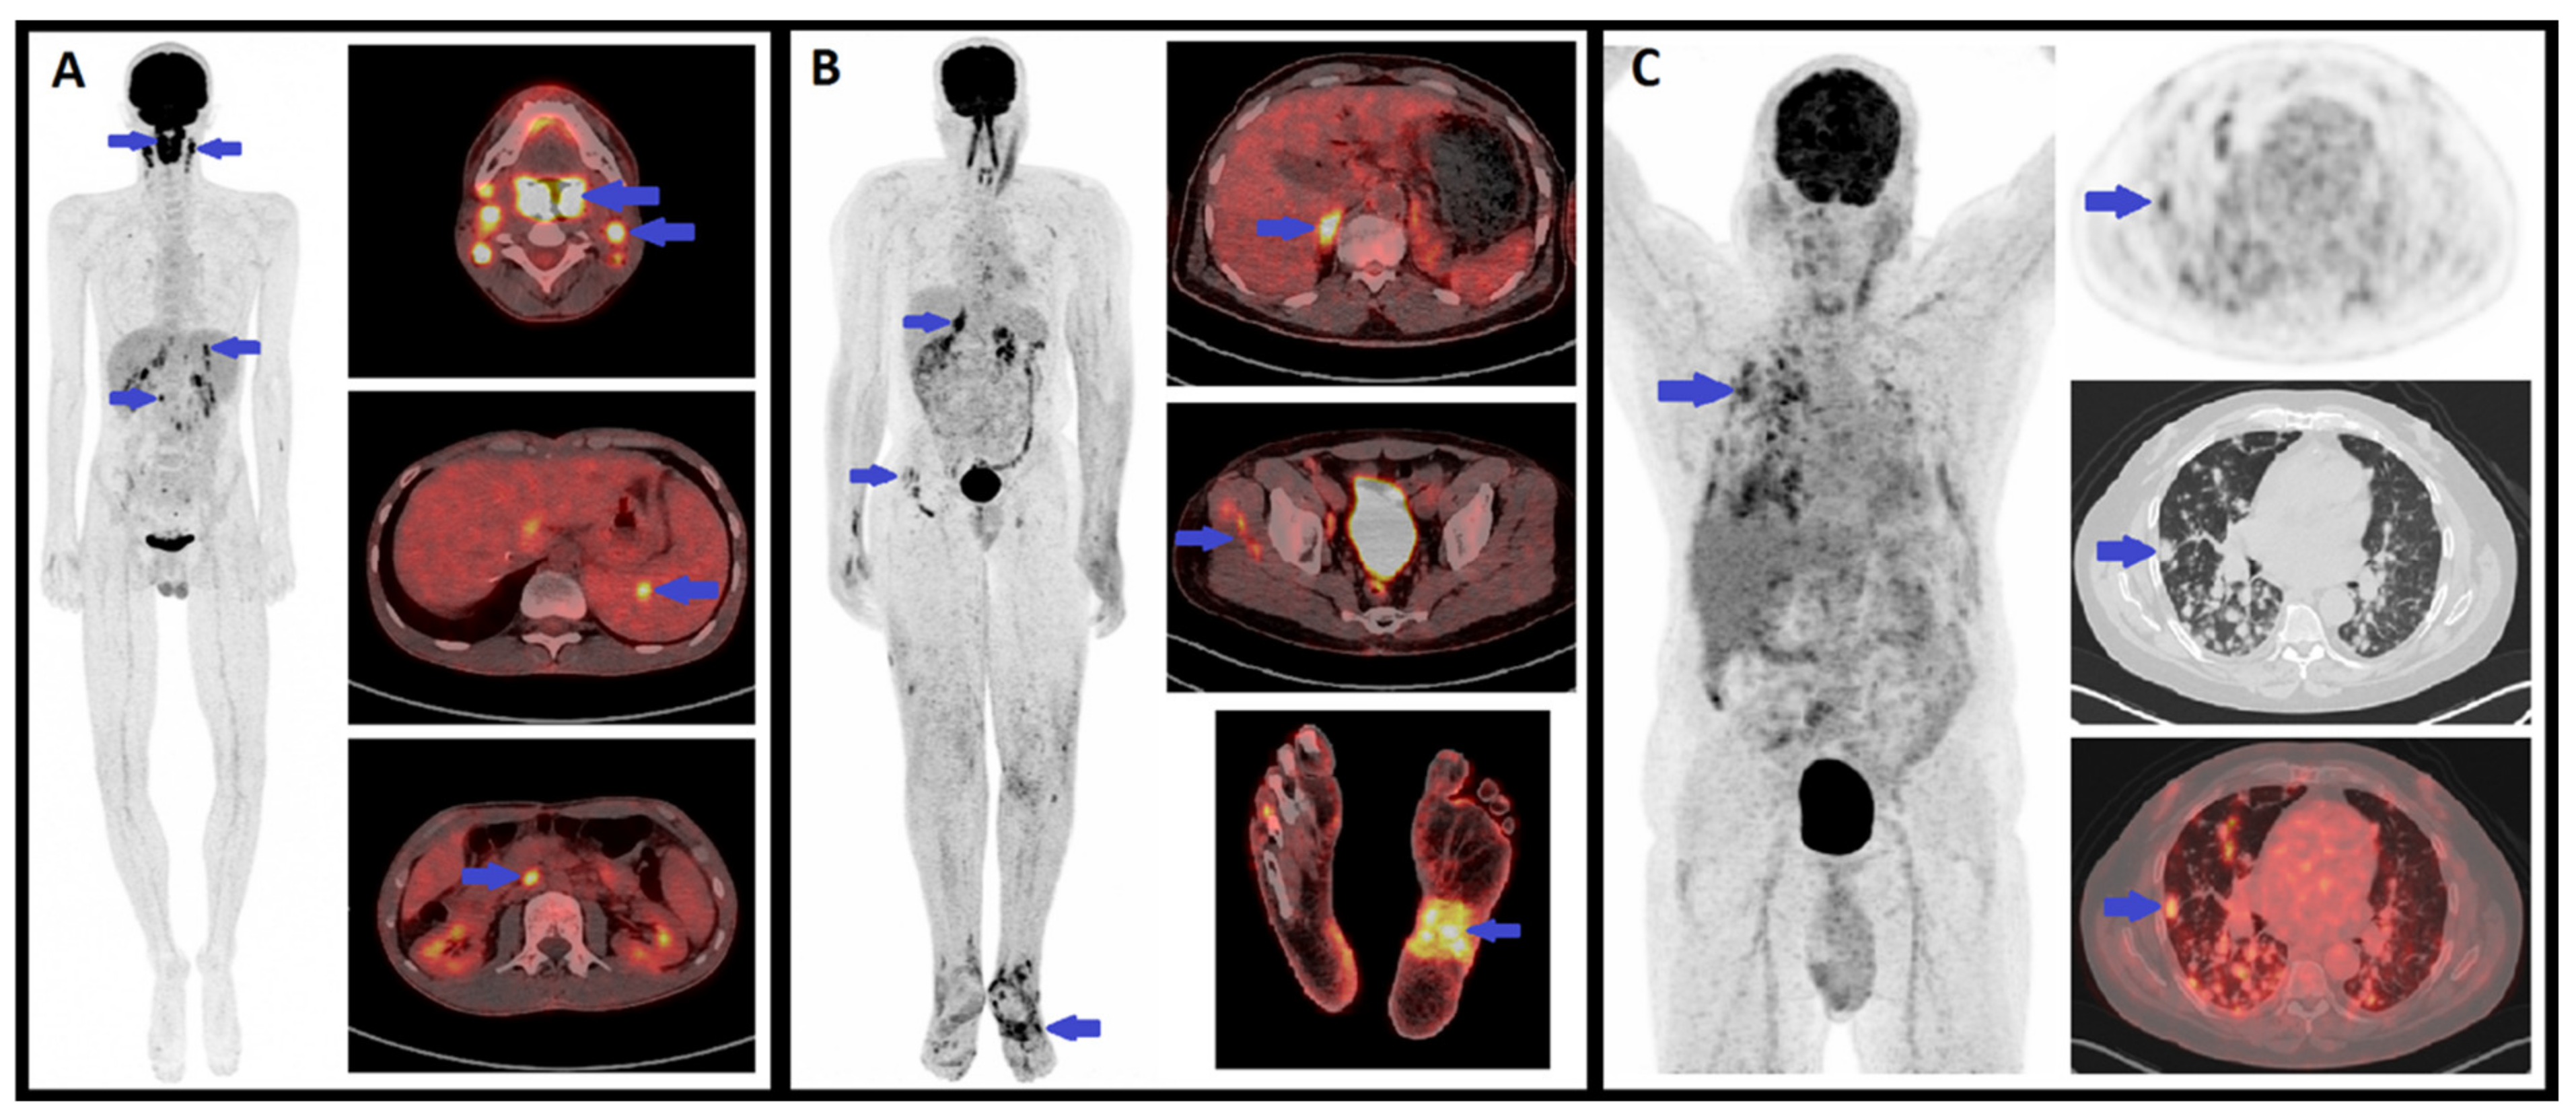

6. FDG-PET